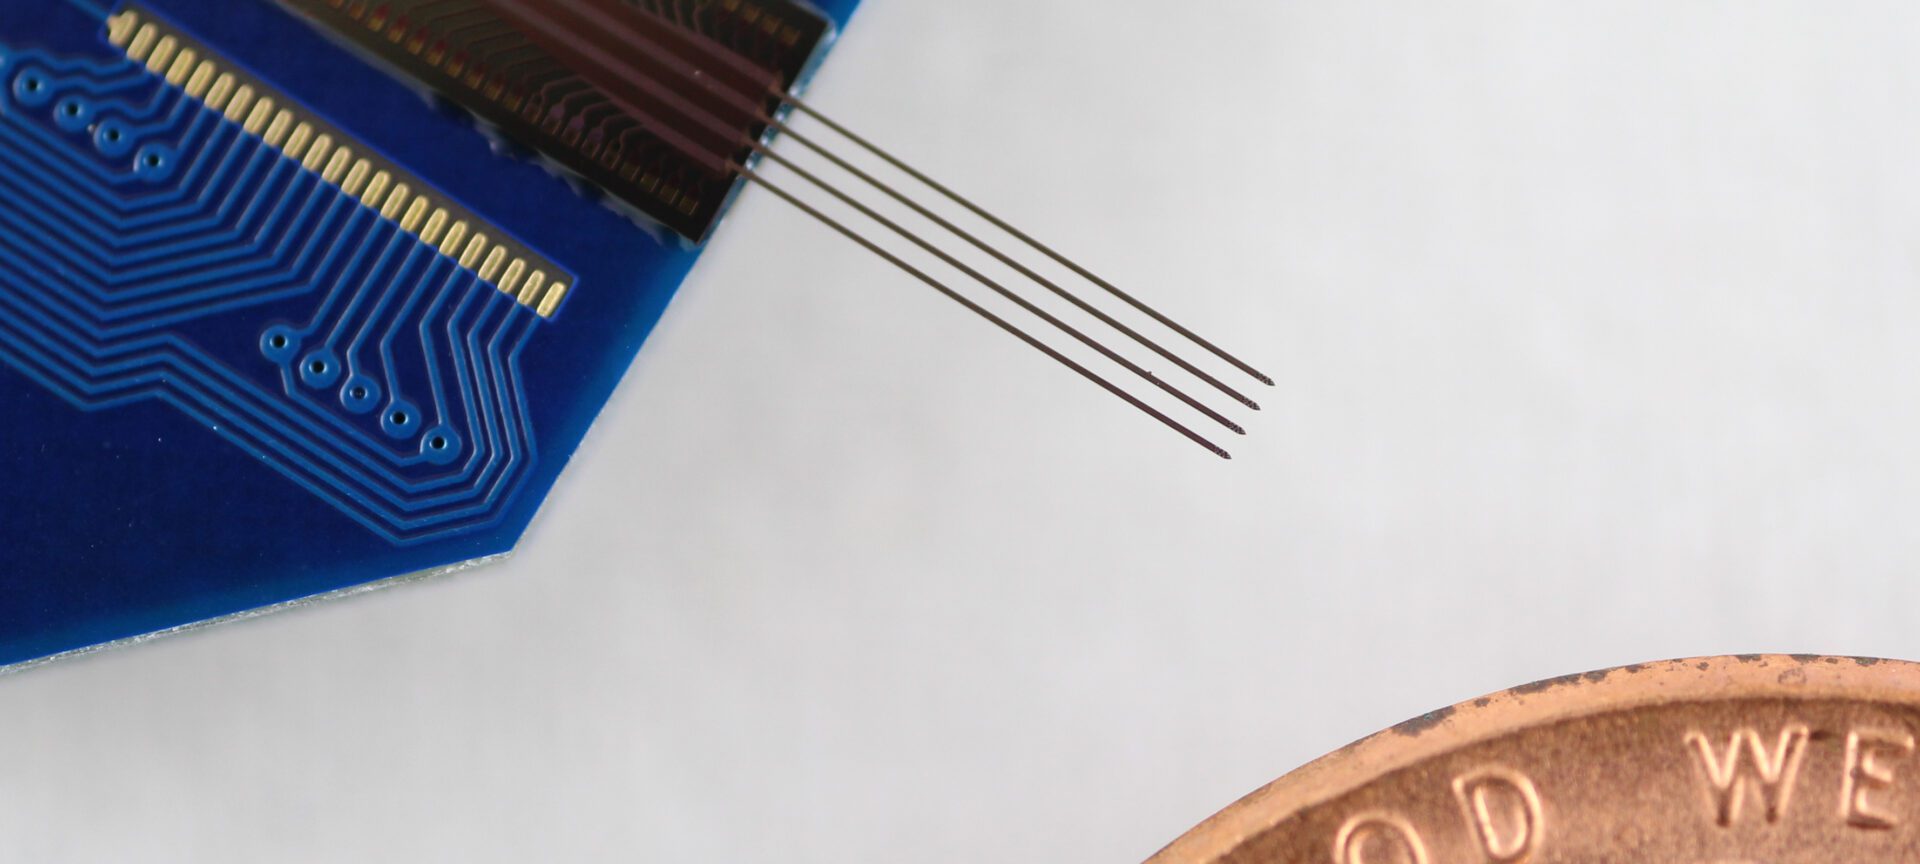

Best paper for a low-power ADC circuit for brain-machine interface applications

Euisik Yoon’s team, led by Sungjin Oh, developed a low-power neural recording front-end circuit to interface with state-of-the-art neural probes.

The post Best paper for a low-power ADC circuit for brain-machine interface applications appeared first on Michigan Engineering News.

The Michigan Probe: Changing the Course of Brain Research

Some believed early Michigan brain researchers were engaging in “science fiction” – until development of an advanced tool for forging breakthroughs proved them wrong.

The post The Michigan Probe: Changing the Course of Brain Research appeared first on Michigan Engineering News.

Improved neural probe can pose precise questions without losing parts of the answers

It will now be possible to study brain activity when timing is important, such as the consolidation of memory.

Research on neural probe that sheds multicolor light on the complexities of the brain recognized for its impact

Prof. Euisik Yoon and his team are recognized for their work designing low-noise, multisite/multicolor optoelectrodes that will help neurologists learn more about neural connectivity in the brain.

Next generation neural probe leads to expanded understanding of the brain

The hectoSTAR probe, with 128 stimulating micro-LEDs and 256 recording electrodes integrated in the same neural probe, was designed for some stellar brain mapping projects